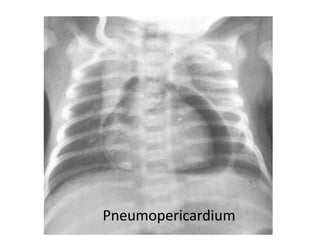

Small right pneumothorax

Pneumomediastinum

Pneumopericardium

Etiology

Spontaneous, MAS, Positive pressure